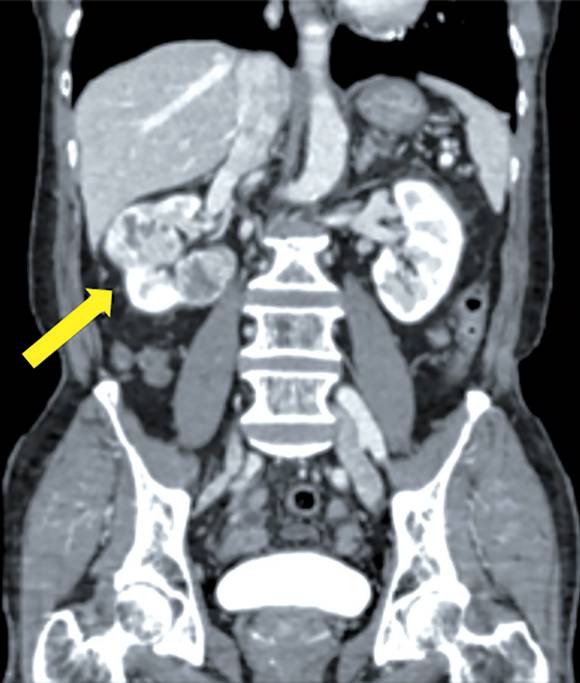

이런 증상은 비뇨기질환(요로 감염, 요로 결석 등)과 비뇨기암(방광암, 전립선암 등)으로도 발생할 수 있다. 따라서 이들 증상만으로 신장암을 진단하지 않는다. 신장암이 의심되는 경우에는 영상 진단을 통해 암 여부를 확인한다. 위험이나 고통이 적고 복부 내 여러 장기를 함께 관찰할 수 있는 영상 진단은 복부 초음파 검사다. 이 검사로 단순 낭종(물혹)인지 고형종물(덩어리)인지를 감별할 수 있다.

복부 초음파 검사에서 단순한 물혹이 아닌 고형종물이 발견되면 CT(전산화단층촬영) 검사를 진행해 악성종양 여부와 병기(병의 진행 정도)를 판단하고 치료 방침을 결정한다. CT 검사로 간, 대장, 췌장 등 주변 장기로 암이 침범 또는 전이됐는지 여부도 알 수 있다. 최근 개발된 인공지능을 결합한 CT는 기존보다 더 높은 정확도를 보인다. 정창욱 교수는 "신장암이 잘 전이되는 부위가 폐와 뼈다. 그래서 신장암을 발견한 후에는 폐와 뼈 전이 여부도 확인한다. 악성종양인지 양성종양인지 애매할 때는 MRI(자기공명영상) 검사를 진행한다"고 설명했다.